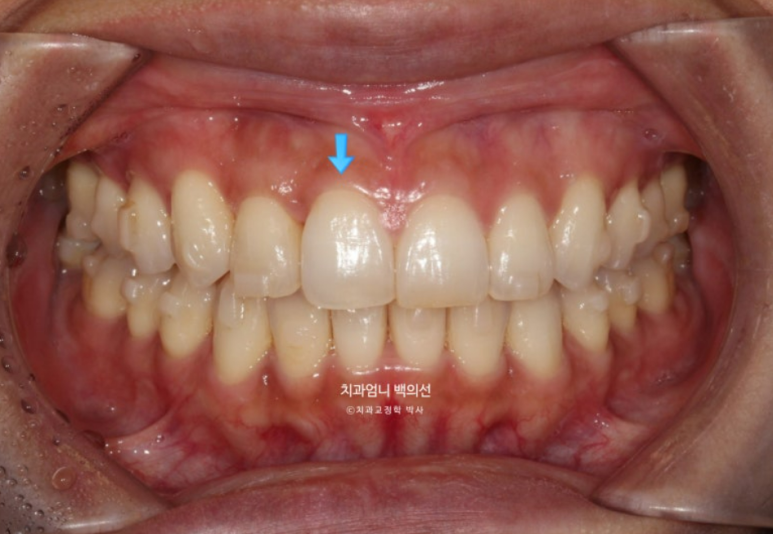

중심선은 잘 맞으나 입천장에 위치했던 축절치가 아직 완벽하게 제자리를 찾지 못했습니다.

덧니의 머리부분은 앞으로 잘 나와 있지만

교합면에서 보면 입천장에 위치했던 덧니 뿌리 부분은 아직 입천장 쪽에 위치해 있습니다.

여담으로 앞니 반대교합이 해소되는 과정에서는 대합치와 엉킨부분이 풀리는 과정에서 서로 먼저 닿는 조기첩촉 시기가 있습니다.

중간 과정상 불가피한 부분이지만 이 시기에는 먼저 닿아 어금니가 잘 안 닿고 해당치아끼리 자주 부딪쳐 불편합니다.

아래치열은 더 이상 고칠 것이 없어보입니다.

스마일 사진을 찍어 중심선 체크도 합니다

덧니쪽으로 쏠려있던 중심선은 이제 중앙을 찾았습니다.